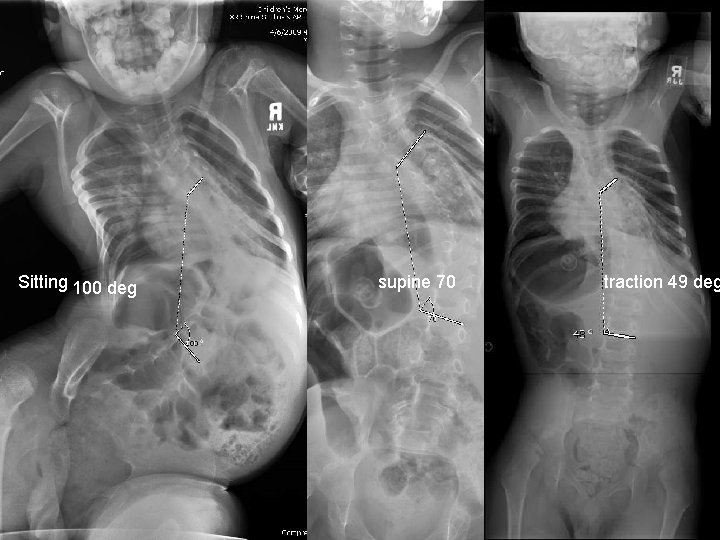

Case 2 : EOS Neuromuscular n n n 4 year 3 month old Microcephalic cerebral palsy Recurrent aspirations and pneumonia Progressive curve of 100° in lower thoracic spine 17 kg

Sitting 100 deg supine 70 traction 49 deg